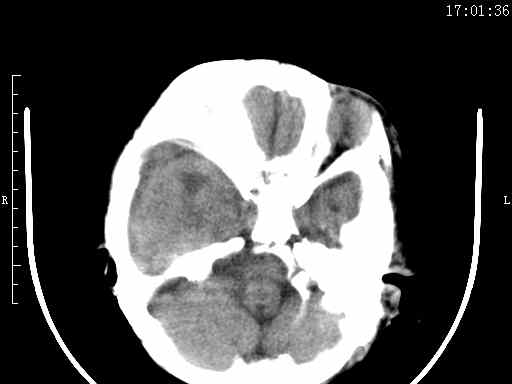

以下是引用余辉在2009-5-30 17:43:00的发言:[br]外围性脑积水在蛛网膜下腔,这个不像,双侧客部液区增宽,内见对称性弧形线状高密度影,边缘清晰锐利,右侧后端终止于冠状缝,左侧终止于人字缝,应该是硬脑膜.双侧硬膜下液区增宽,脑皮质受压变平,脑沟裂无显著增宽,考虑1双侧额颞顶部慢性硬膜外血肿伴硬膜下积液或慢性血肿2双侧慢性硬膜下积液伴硬脑膜剥离并有交通积液(反正考虑硬膜下及硬膜外的慢性血肿或积液)